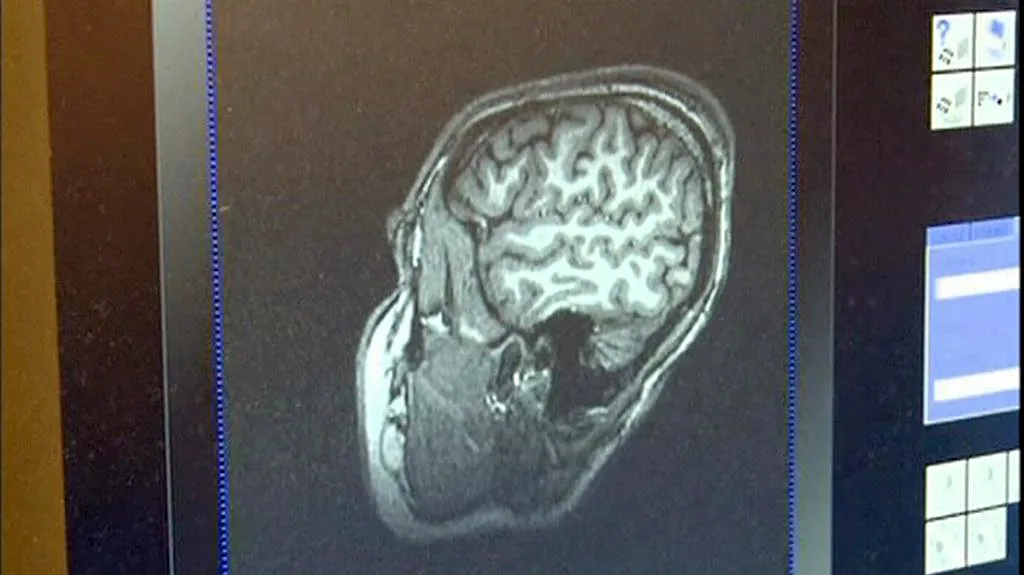

Posttraumatická stresová porucha může nastoupit až půl roku po prožité dramatické události. Nemocný nemůže spát, nesoustředí se, může se objevit deprese, úzkost nebo různé závislosti. Pomáhat mají antidepresiva a psychoterapie. Vědci na Univerzitě Johnse Hopkinse v Baltimoru teď tvrdí, že našli další možnost – chtějí stresovou reakci z mozku prostě vymazat. Tým neurologa Richarda Huganira se zaměřil na bílkovinu, která se objeví ihned po traumatu v amygdale – té části mozku, kde se formuje paměť spojená s emocionálním zážitkem.